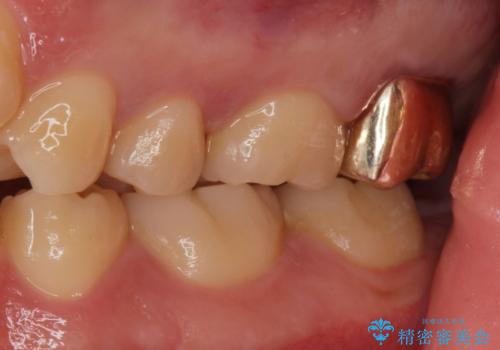

- 銀歯を良いものに変えたいとの事で来院。

過去に根の治療もされている歯だが土台が粗造なため根の治療からやり直しを行いゴールドクラウンにて治療を行いました。

また手前のはに虫歯があったためセラミックの詰め物で治療しました。

適合の良い被せ物が入りました。

ゴールドの被せ物は適合がよく虫歯の再発のリスクが低くなります。